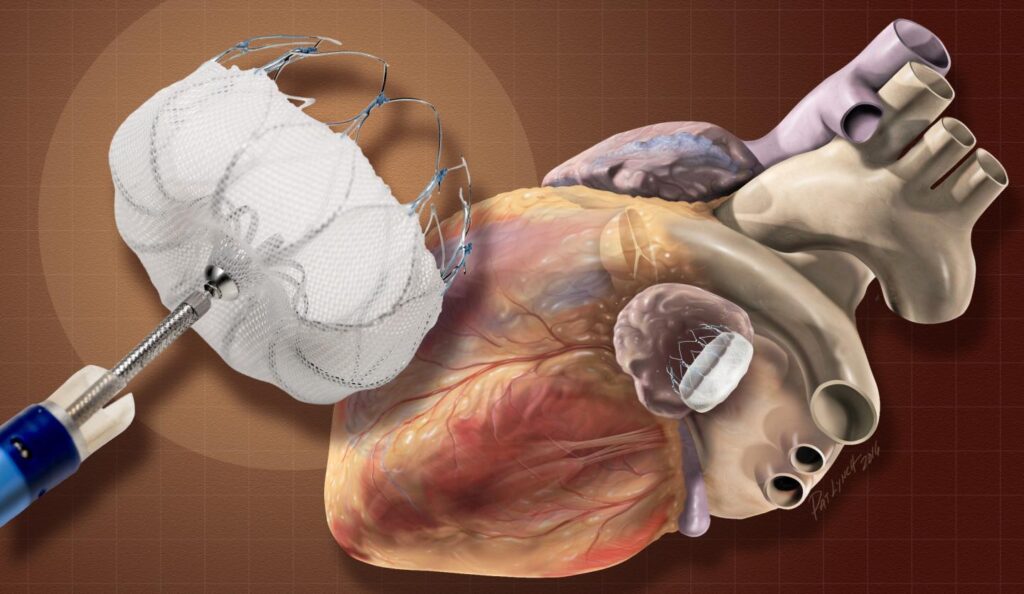

Neurovascular devices play a critical role in the diagnosis and treatment of complex neurological conditions such as aneurysms, strokes, and arteriovenous malformations (AVMs). These devices, which include catheters, embolization devices, and stent retrievers, enable minimally invasive procedures that reduce patient recovery times and improve clinical outcomes. The growing global burden of neurovascular diseases, especially among the aging population, is a key factor driving the adoption of these devices.

The market is also benefiting from technological advancements in neurovascular intervention tools, which are enhancing procedural precision, improving safety, and enabling faster recovery for patients. The demand for less invasive, image-guided procedures is encouraging healthcare providers to integrate state-of-the-art neurovascular devices into their surgical workflows.

- Shift Towards Minimally Invasive Procedures: There is a growing preference among healthcare providers and patients for minimally invasive techniques over traditional surgeries. Neurovascular devices facilitate these procedures, offering lower risks and shorter recovery times.

- Technological Advancements: Innovations in neurovascular devices, including the development of new stent designs and embolization techniques, are enhancing treatment efficacy and safety, further propelling market growth.

- Aneurysm Coiling and Embolization Devices

- Neurothrombectomy Devices